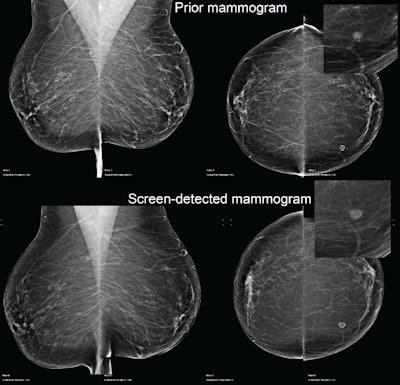

At Sunday morning's session, he presented the findings of a retrospective study about AI's accuracy in detecting breast cancer. The trial used 2,683 screening mammograms from Optimam, an image database of over 80,000 digital images extracted from the U.K. National Breast Screening System (NBSS). The images used were biopsy-proven, screen-detected cancers.

Of the screen-detected cases, 1,969 presented with invasive cancers and 670 contained ductal carcinoma in situ (DCIS) only. There were a total of 1,001 presented grade 3 cancers, 1,186 grade 2 cancers, and 314 grade 1 cancers.

Each mammogram was analyzed by an AI system (Transpara, ScreenPoint Medical). The software, which received 510(k) clearance from the U.S. Food and Drug Administration (FDA) in November 2018, produced a decision at different recall rates. Recall-rate calibration was established for a typical screening population with another set of independent data, but the mammograms in this study were never before used to train, validate, or test the AI system, according to Halling-Brown.

He reported that the AI system had a sensitivity for screen-detected cancers of 99.3%, 87.7%, and 76.1% at recall rates of 50%, 10%, and 4%, respectively.